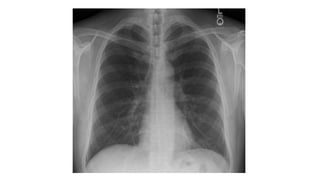

This document discusses key aspects of thorax radiology including positioning for PA and AP views, assessing heart size, visibility of anatomical structures like the scapulae, lungs zones, and measurements like cardiothoracic ratio. It provides guidance on evaluating rotation, inspiration, and penetration on chest x-rays as well as identifying structures like the lobe of azygos vein and aortic knuckle.